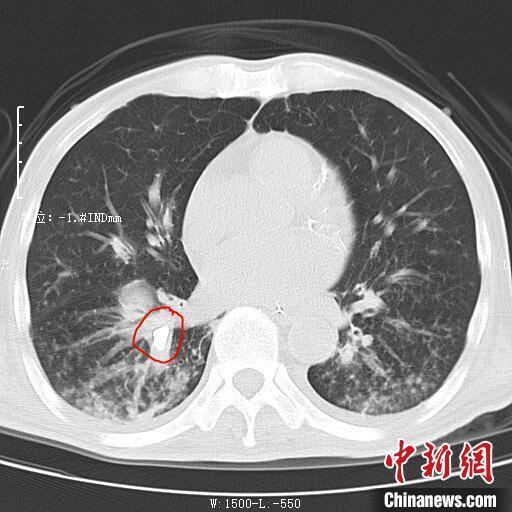

入院后,该院重症医学科主任毕立杰带领团队对患者进行了检查。通过胸部DR平片发现,患者的右肺下叶有一异物,形状不规则。为了进一步明确异物位置,患者接受了胸部CT三维重建检查,检查可见异物在右肺下叶内带,形状与牙齿极其相近。

该患者的胸部CT图。西安中医脑病医院供图